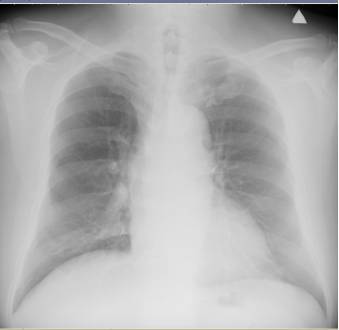

胸部正侧位片

未见胸部活动性病变(图2)。

图2